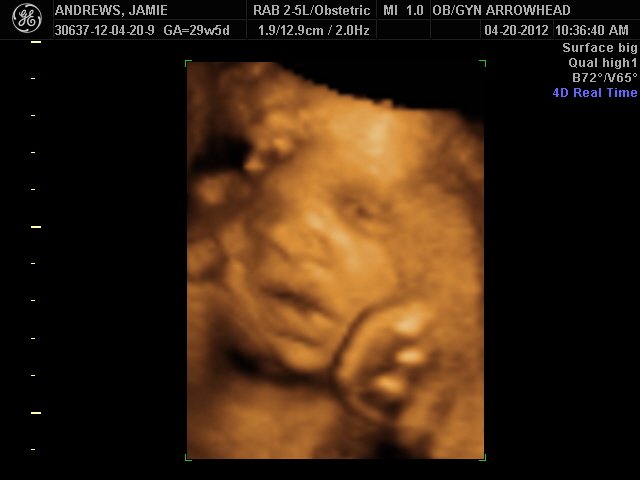

We offer complimentary 3D/4D Ultrasounds to all our OB patients around 30 weeks! The following photos are some examples of our work, shown with permission from our patients.